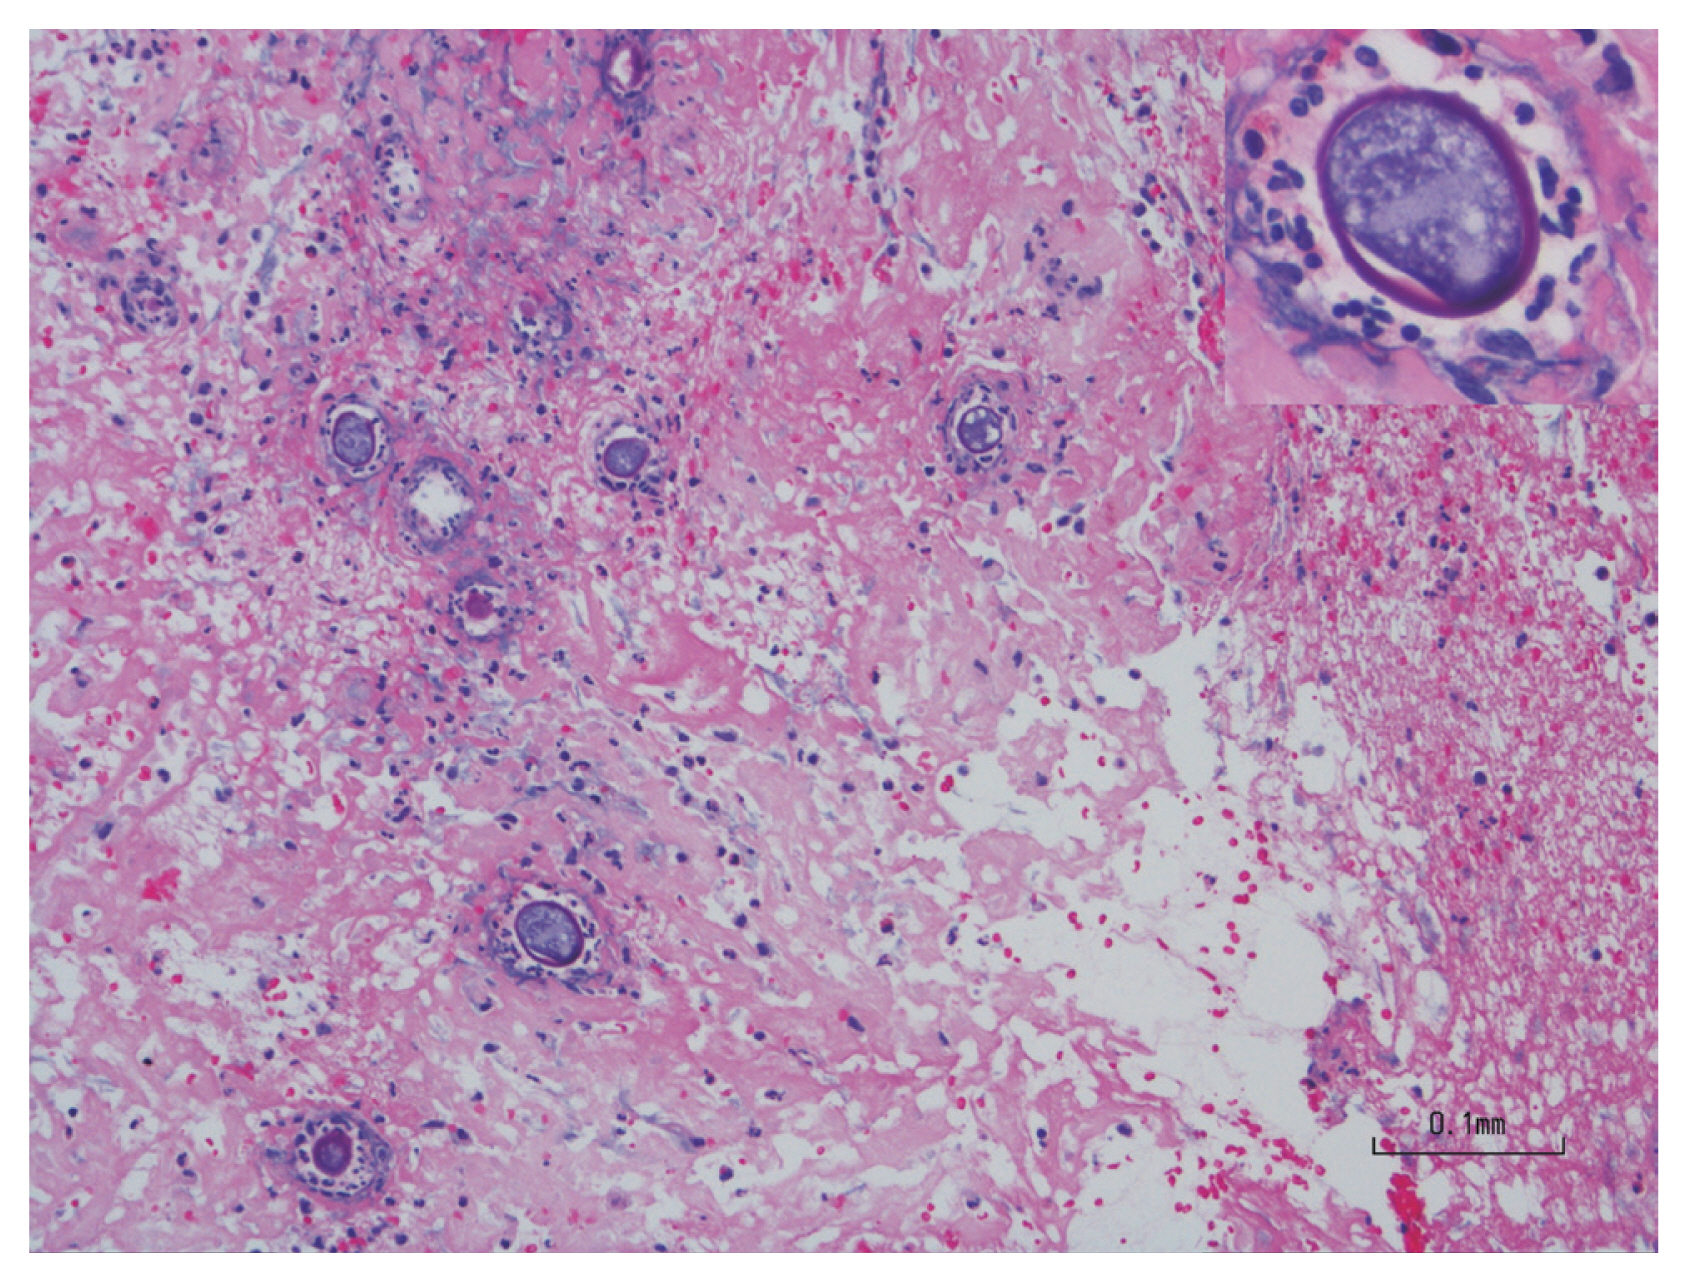

A previously healthy, 36-year-old Latino human immunodeficiency virus-negative man from the Southern United States with no recent travel history presented with one month of abdominal pain, nausea, vomiting, post-prandial emesis, and unintentional weight loss. He denied smoking, use of non-steroidal anti-inflammatory drugs, and history of Helicobacter pylori infection. Abdominal imaging showed a 2.2-cm gastric antral mass with evidence of gastric outlet obstruction (Fig. 1A). Upper endoscopy identified an ulcerated pyloric channel mass with raised edges causing gastric outlet obstruction (Fig. 1B). Biopsies from the ulcerated mass demonstrated necroinflammatory debris, round structures with well-defined boundaries, and underlying stroma with increased eosinophils. Periodic acid-Schiff (PAS) and Grocott’s methenamine silver stains were negative, and there were no signs of underlying malignancy. Repeat upper endoscopy with biopsies revealed similar findings. Despite conservative management with nasogastric tube decompression and intravenous proton pump inhibitor therapy, the patient’s symptoms persisted, and he underwent distal gastrectomy with loop gastrojejunostomy. By the third day after the surgery, the patient was tolerating regular diet. Final surgical pathology revealed coccidioidomycosis-associated chronic active gastritis and gastric ulcers. PAS stains showed large coccidioidomycosis spherules (up to 80 microns) with many endospores (Fig. 2). The patient’s symptoms had significantly improved post-operatively, and after the diagnosis of coccidioidomycosis was established, treatment was initiated with fluconazole 400 mg daily for 2 months. Outpatient follow-up was requested in the infectious diseases clinic. The diverse clinical manifestations of coccidioidomycosis make diagnosis particularly challenging. Gastrointestinal coccidioidomycosis is especially rare and there are scarce reports of cases presenting as small bowel obstruction or as gastric ulcers. In order to increase clinician awareness, we highlight a very distinctive gastrointestinal manifestation of coccidioidomycosis presenting as gastric outlet obstruction.

Figure 1

(A) Computed tomography imaging showing a 2.2-centimeter gastric antral mass with evidence of gastric outlet obstruction (arrows), (B) esophagogastroduodenoscopic findings of an ulcerated pyloric channel mass with raised edges.